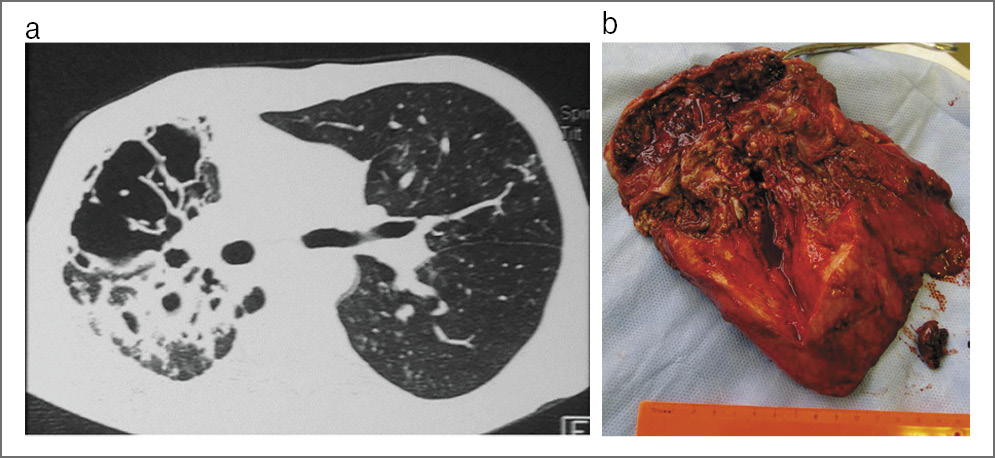

– Я понимаю, о чем Вы говорите. Но я могу доказать свою точку зрения. Приведу небольшую статистику лечения лекарственно-устойчивого туберкулеза легких на нашей базе НИИФП ФГАОУ ВО «Первый МГМУ им. И.М. Сеченова» (Сеченовский Университет) с 2011 по 2017 г. В основном это пациенты с разным типом лекарственной устойчивости (табл. 1). Почти у 70% всех больных – ФКТ (рис. 3), у 25% – туберкулема (рис. 4). Особую опасность представляет казеозная пневмония, так как без оперативного вмешательства смертность может достигать 99% (рис. 5).

Рис. 4. Туберкулема с распадом легкого: а – на КТ органов грудной клетки; b – на макропрепарате.